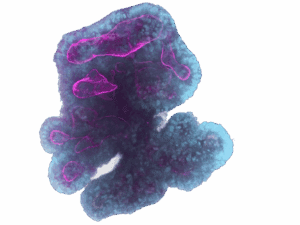

ProxyDiscovery provides patient-derived organoid models that mirror real tumor biology. By generating functional readouts of drug response, we enable more accurate predictions of clinical outcomes and guide better decision-making at every stage of discovery.

Using patient-derived organoids, we validate drug targets and identify compounds with the greatest likelihood of success. By prioritizing leads based on organoid response data and filtering out false positives from traditional models, we streamline the transition from discovery to development with higher confidence.

We test lead compounds across diverse patient populations to capture variability in response. Through predictive modeling of therapeutic windows and safety profiles, we help identify patient subgroups most likely to benefit, reducing risk and improving outcomes.